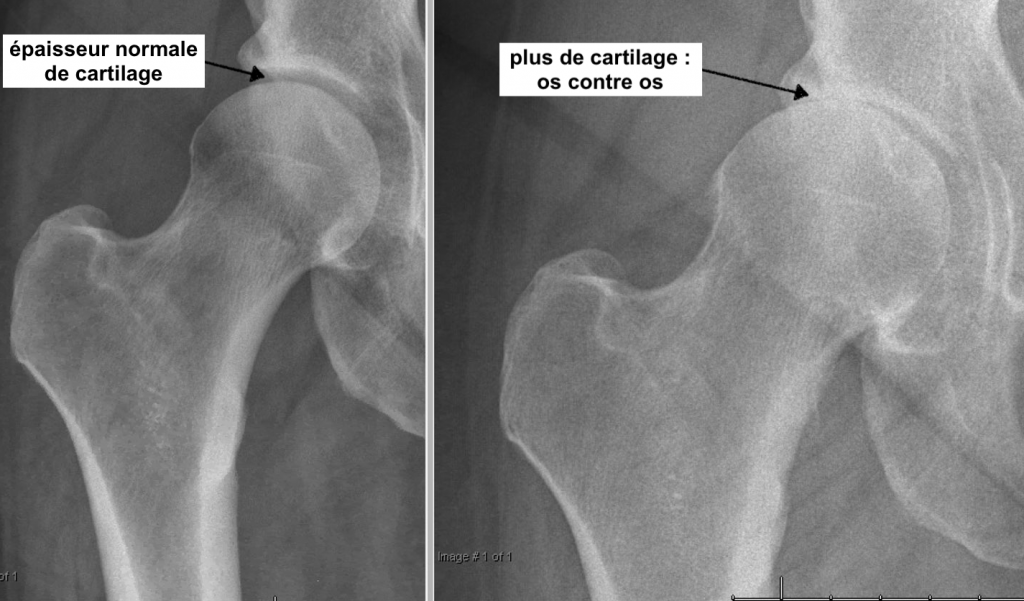

La hanche fonctionne comme une balle dans une cavité. La balle, c’est la tête du fémur, et la cavité, c’est l’acetabulum ou cotyle, qui appartient à l’os du bassin. Les deux os sont recouvertes d’un cartilage, un revêtement très lisse, qui permet à la hanche de bouger et marcher sans frottement. L’arthrose, c’est quand ce cartilage s’use, se raye ou se fissure. Si la surface n’est plus lisse, les mouvements de la hanche « accrochent » et on peut avoir mal en marchant, et une raideur.